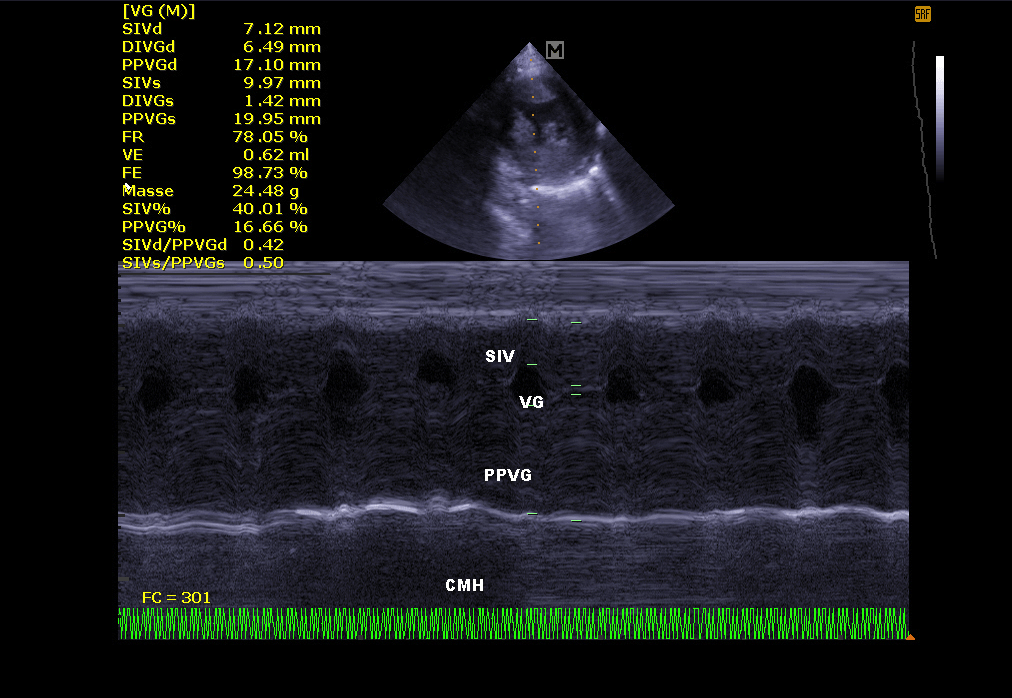

Échographie cardiaque:

Elle permet de visualiser les différentes parties du cœur (parois, cavités, valvules) et de repérer d’éventuelles anomalies qui empêchent un fonctionnement cardiaque correct . En cas d’insuffisance cardiaque, l’échocardiographie permet aussi un suivi régulier de la morphologie cardiaque. Il est alors plus facile de réajuster le traitement mis en place.